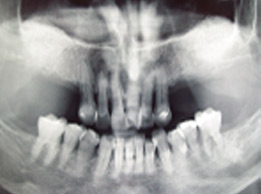

prije